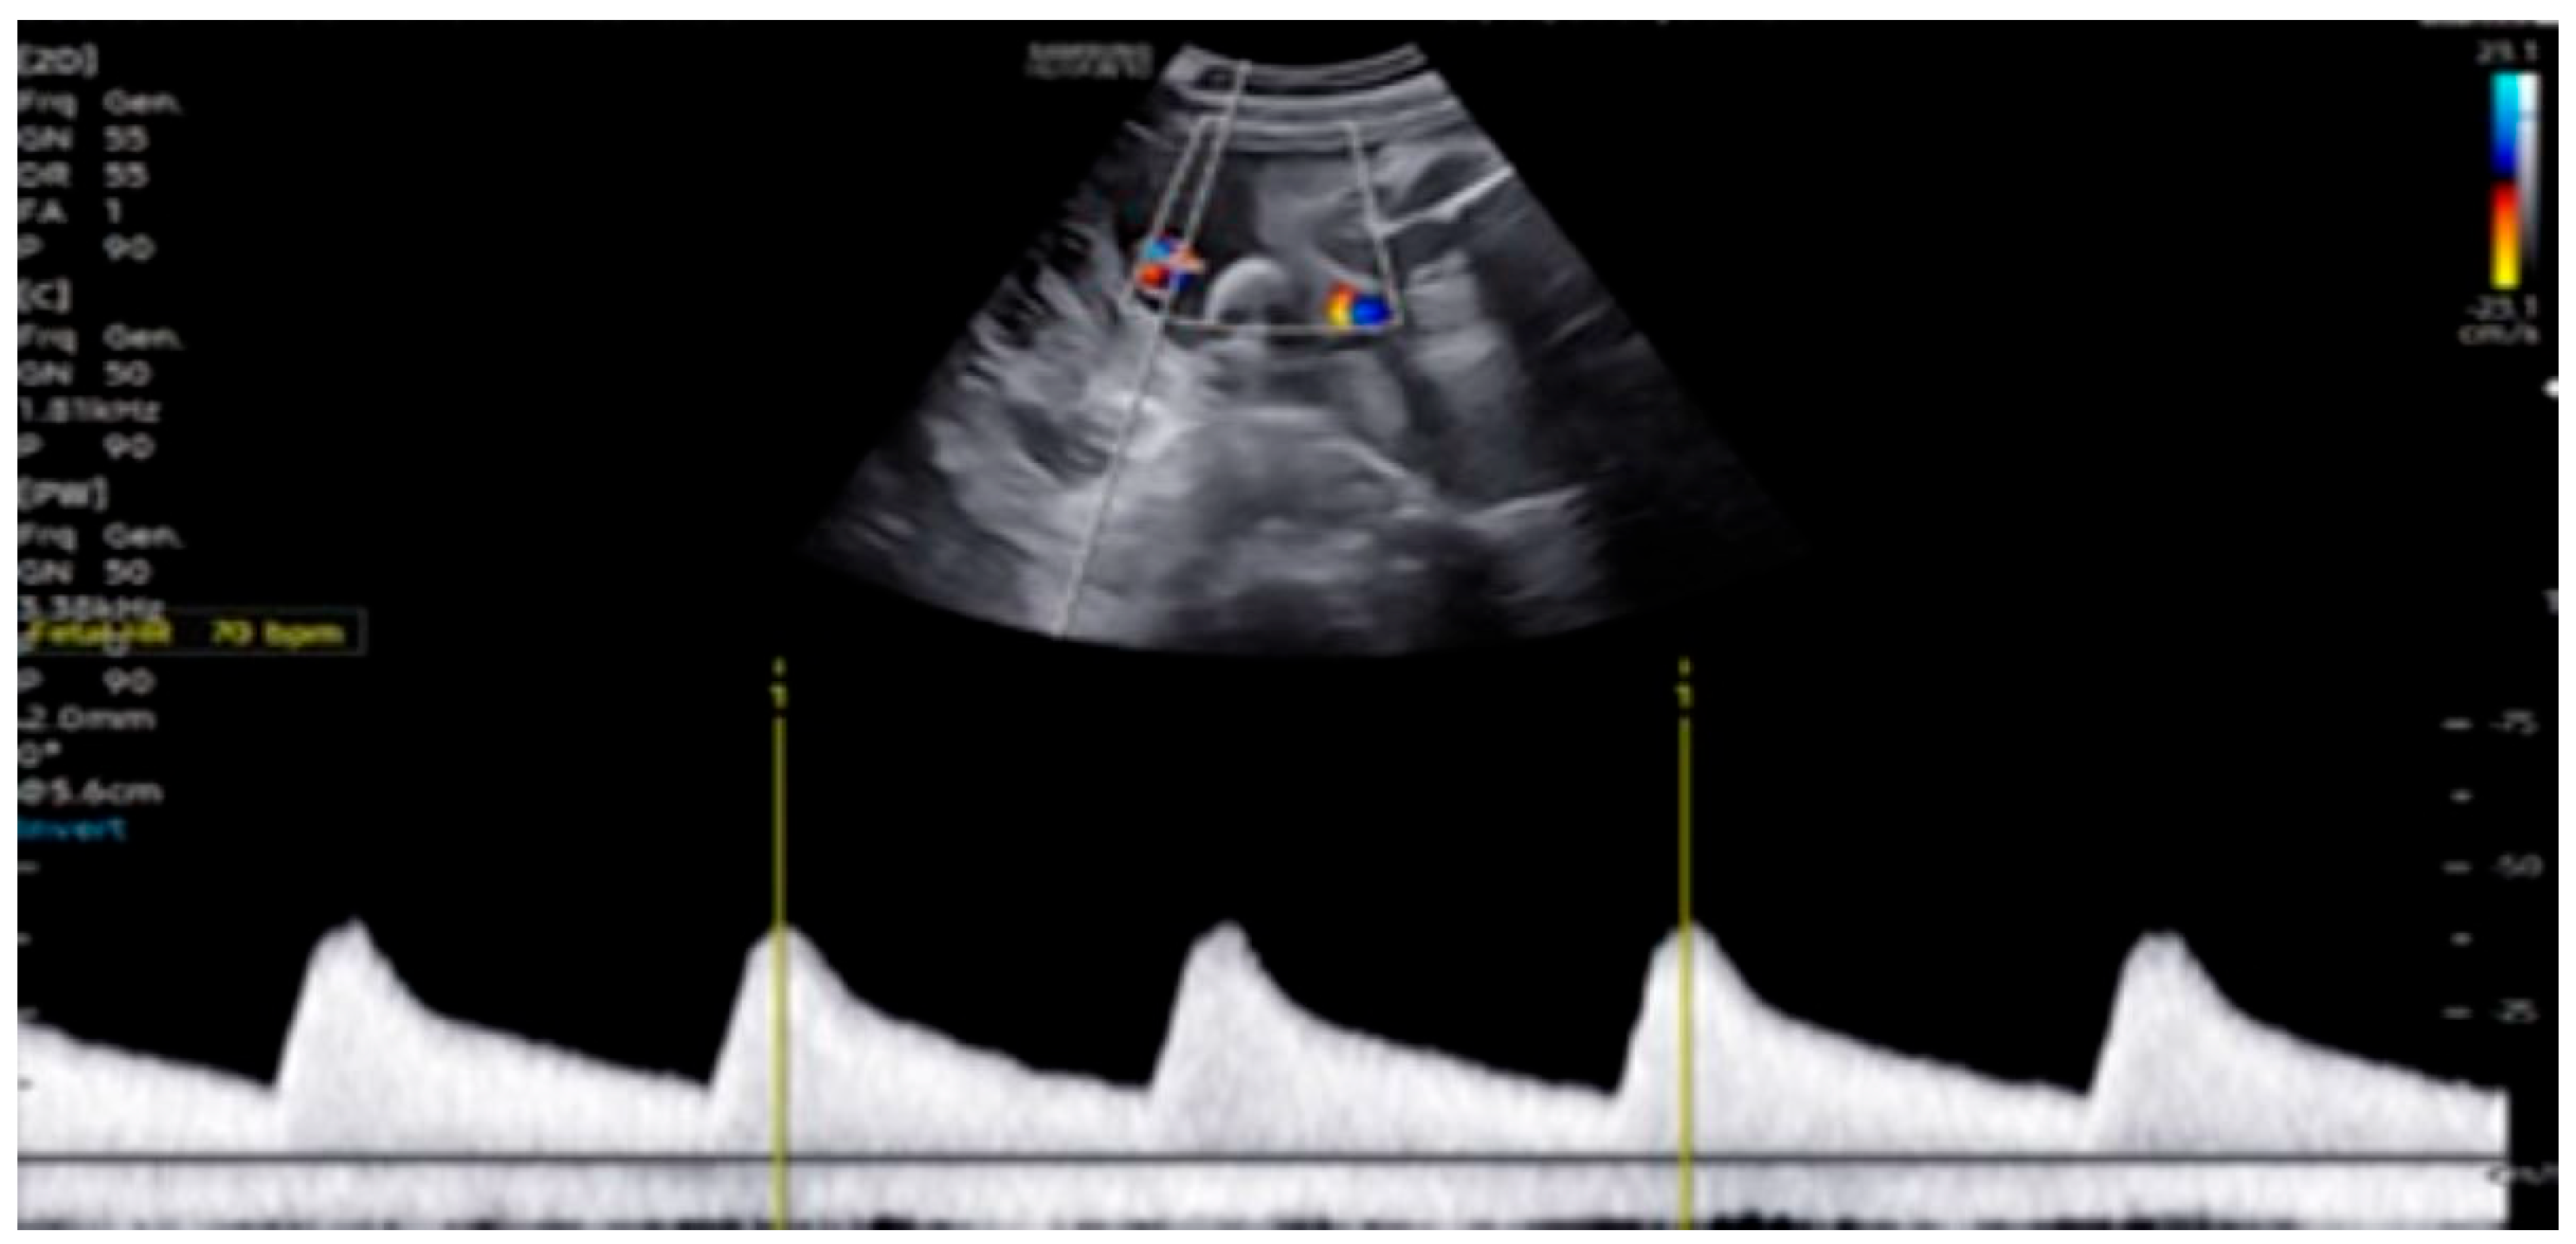

| 26 + 0 | Start of dexamethasone 4 mg/day | 60 | SF increased from 34% to 47%, but qualitative contractility decreased | Mild edema; no beta- agonists used |

| 28 + 0 | First IVIG cycle (65 g total) | 75 | SF increased to 52%; mild improvement in contractility | Initiated due to signs of fibroelastosis |

| 31 + 2 | Post-IVIG peak response | 70 | SF: 59% (LV), 52% (RV); marked biventricular improvement | Aortic isthmus 3 mm (Z-score –1.65) |